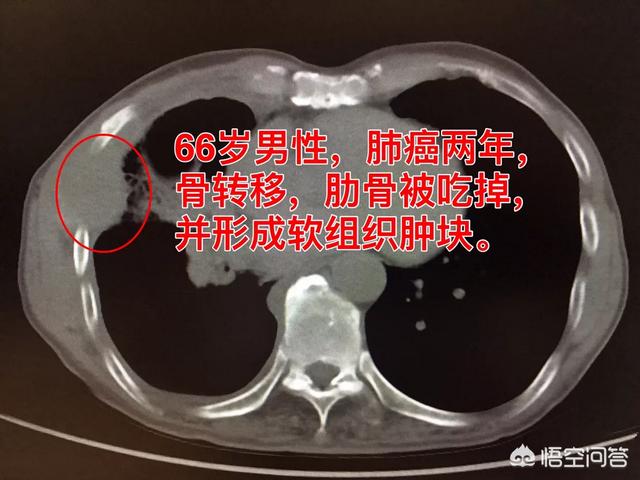

Sur le site des métastases osseuses, étant donné que le tissu osseux normal est détruit et remplacé par du tissu tumoral et que les cellules tumorales prolifèrent constamment, des ombres de masses de tissus mous peuvent être observées sur de nombreux sites de métastases osseuses, et peuvent être palpées si la masse se trouve dans une zone superficielle. En outre, l'érosion du tissu osseux normal par le tissu tumoral entraîne également la destruction et l'affaiblissement de la structure osseuse normale, de sorte que des fractures peuvent se produire sous l'effet de forces externes normales, appelées fractures pathologiques (figure ci-dessous). Outre la douleur et la fracture pathologique, les métastases au niveau de la colonne vertébrale peuvent également se manifester par une compression des racines nerveuses de la colonne vertébrale avec des symptômes tels qu'une déficience sensorielle, une faiblesse musculaire et, dans certains cas, une hypercalcémie.

Je suis le Dr Shadow. Les métastases osseuses sont un stade avancé du cancer. Les cellules cancéreuses se répandent dans la circulation sanguine, colonisent les os et s'y développent, provoquant une destruction osseuse ostéolytique ou une augmentation ostéoblastique de la densité osseuse. Il est regrettable que de nombreux patients atteints d'un cancer se soient révélés avoir un cancer du poumon à un stade avancé en raison de douleurs au dos et aux jambes.

3. masses localisées dans les tissus mous

Les métastases osseuses entraînent la dégradation de l'os et les cellules cancéreuses se développent localement pour former une masse de tissu mou, un autre nid de cancer. C'est la raison pour laquelle il y a des bosses en plus de la douleur, et c'est à ce moment-là qu'il faut être attentif aux métastases osseuses.